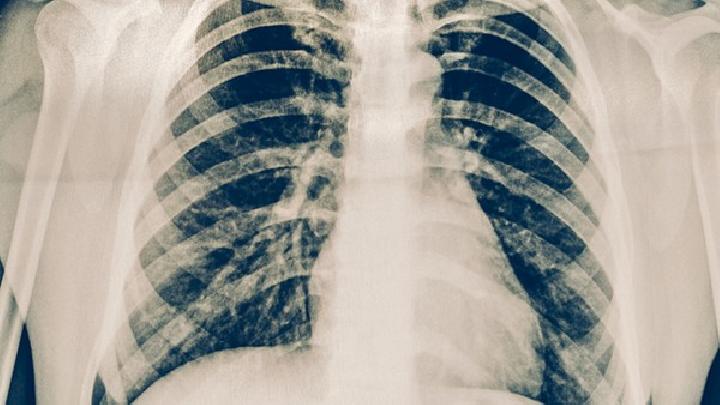

耐药性肺结核的治疗时间通常较长,平均需要18到24个月,具体时长取决于患者的病情严重程度、耐药类型以及治疗依从性。耐药性肺结核的治疗周期之所以较长,是因为其病原体对抗生素产生抗药性,常规药物难以有效控制病情,需要采用更复杂的治疗方案。